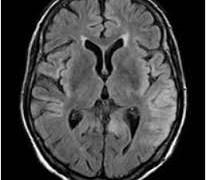

症状 高血圧の人、こんな症状は要注意!:めまい・吐き気・しびれ・頭痛 そもそも高血圧の症状って何? めまい、頭痛、吐き気?高血圧は、”サイレントキラー”とういう異名を持つのでしたね。すなわち、高血圧は症状がないのです。しかし、これは高血圧がひどくない場合であって、末期の高血圧では当然症状が出るようになります... 2015.10.10 症状